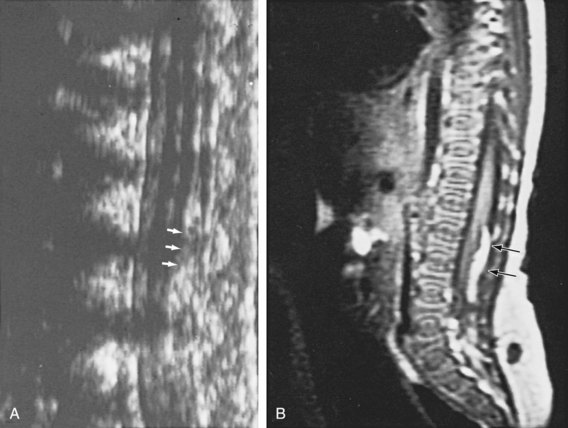

The neurologic lesion in myelodysplasia is a dynamic disease process in which changes take place throughout childhood (Epstein, 1982; Reigel, 1983; Venes and Stevens, 1983; Oi et al, 1990), especially in early infancy (Spindel et al, 1987) and later at puberty (Begger et al, 1986), when the linear growth rate accelerates again. When a change is noted on neurologic, orthopedic, or urodynamic assessment, radiologic investigation of the CNS often reveals (1) tethering of the spinal cord (Fig. 128–6), (2) a syringomyelia, a dilation and fluid collection within the spinal cord, (3) increased intracranial pressure due to a shunt malfunction, or (4) partial herniation of the brainstem and cerebellum. Children with completely intact or only partially denervated sacral cord function are particularly vulnerable to progressive changes. Magnetic resonance imaging (MRI) is the test of choice because it reveals anatomic details of the spinal column and CNS (Just et al, 1990). However, it is not a functional study and when used alone it cannot provide exact information about a changing neurologic lesion.

Figure 128–6 MR image in a 9-year-old girl who developed a tethered cord after myelomeningocele repair reveals the conus opposite the L3–4 vertebrae (arrow).

Figure 128–15 A, During the first few months of life, ultrasonography can clearly demonstrate intravertebral anatomy because the posterior arches have not completely ossified. Note that the spinal cord along with its central canal is displaced anteriorly (white arrows) beginning at L3 because of an intradural lipoma. B, The MR image is juxtaposed to confirm the ultrasound findings. The longitudinal white intraspinal mass (black arrows) is the lipoma; the longitudinal gray mass is the spinal cord.